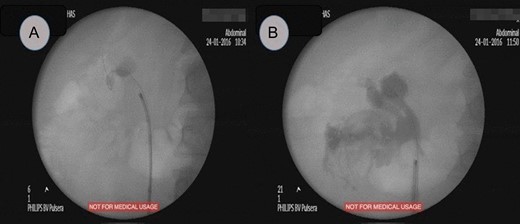

Fluoroscopic study, (A) showed a radiopaque shadow at level of L2, (B) showed extravasation of contrast at the end of surgery.